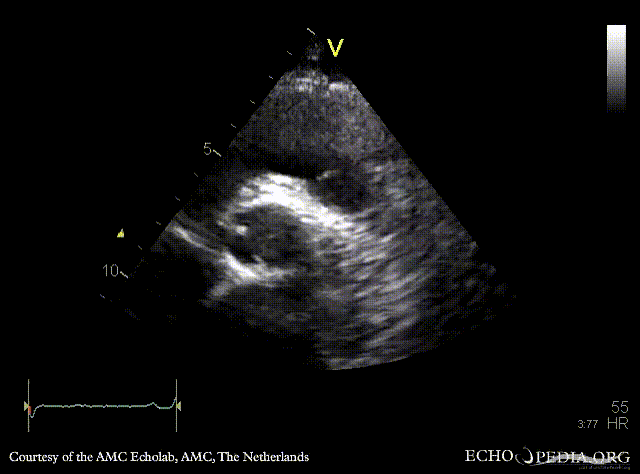

Davids procedure

Courtesy of: AMC Echolab, AMC, The Netherlands

PLAX: native aortic valve and prosthesis in ascending aorta PLAX with Color Doppler